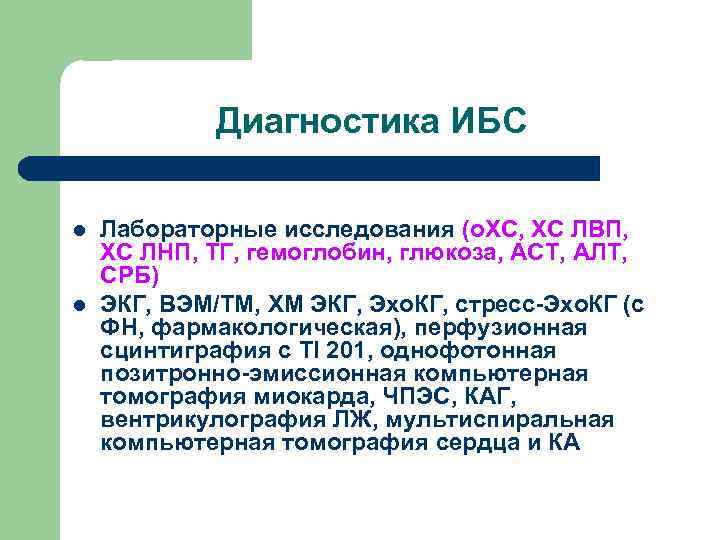

Диагностика ИБС l l Лабораторные исследования (о. ХС, ХС ЛВП, ХС ЛНП, ТГ, гемоглобин, глюкоза, АСТ, АЛТ, СРБ) ЭКГ, ВЭМ/ТМ, ХМ ЭКГ, Эхо. КГ, стресс-Эхо. КГ (с ФН, фармакологическая), перфузионная сцинтиграфия с Tl 201, однофотонная позитронно-эмиссионная компьютерная томография миокарда, ЧПЭС, КАГ, вентрикулография ЛЖ, мультиспиральная компьютерная томография сердца и КА